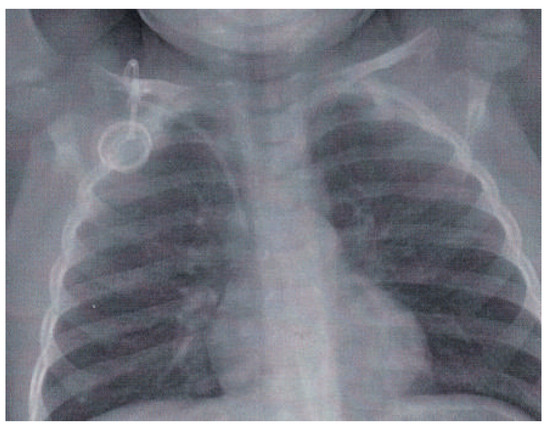

A Patent Foramen Ovale May Be Dangerous ... Even in Childhood

by Jean-Pierre Pfammatter and Bernhard Meier

A 2-year-old boy was diagnosed with acute lymphatic leukaemia [...] Full article